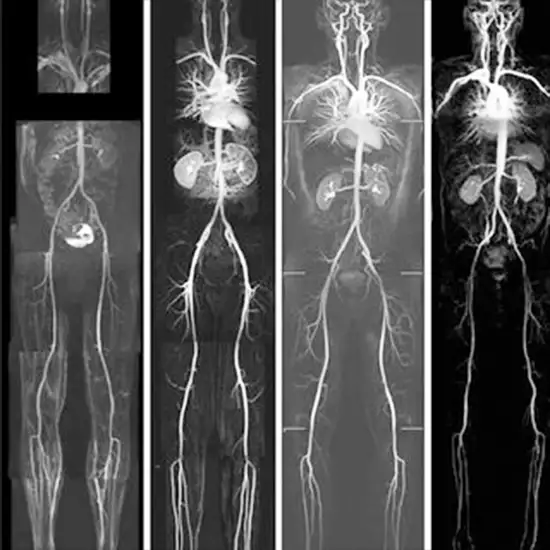

Whole Body CT Angiography is an imaging scan used to examine the functioning of the blood vessels and arteries throughout the body. It depicts all vascular regions of the body in a single, quick procedure. This scan detects blood vessel problems such as narrowing and fat deposition in the arteries. You will be injected with contrast media to obtain cross-sectional images of the vessels during the Whole-body CT Angiography procedure.

This scan allows doctors to look for blockages, clots, aneurysms, congenital cardiovascular abnormalities, disorganised blood vessels, tumours, vessel ruptures, or injury in the blood vessels.

When doctors suspect severe vascular disorders/diseases that cause abnormalities in various parts of the body, whole body CT Angiography is recommended. This scan includes the blood vessels and aorta, the renal arteries, the carotid arteries, the peripheral arteries, the visceral arteries, the subclavian arteries, and the transplanted arteries.